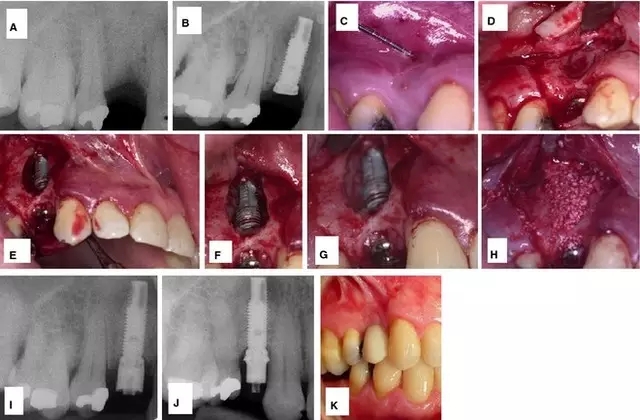

此外,也有學(xué)者應(yīng)用凍干骨和膠原膜也成功修復(fù)了骨缺損。但是 Balshi 等學(xué)者認(rèn)為相比引導(dǎo)骨再生,手術(shù)切除感染種植體的根尖區(qū)是更好的治療方法。他們的治療程序如圖 2:】

圖 2 :(A)種植體植入后即刻負(fù)載三月后的根尖周 x 線片;(B–E)移除 21,切除 23 根尖 ;(F)術(shù)后調(diào)整和修復(fù); (G) 術(shù)后口內(nèi) x 線片;(H–J)種植體根尖切除后 2 (H)、4 (I)、 6 (J)年的曲面斷層